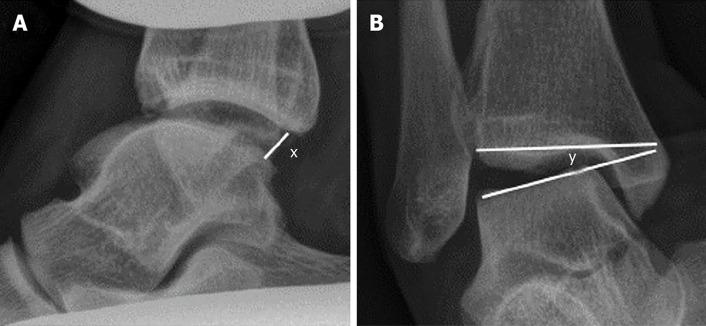

Correlation of stress radiographs to injuries associated with lateral ankle instability.

A retrospective review of 87 consecutive patients aged 18-74 who had stress radiographs performed at a single institution between 2014 and 2020 was performed. These manual radiographic stress views were then correlated with magnetic resonance imaging and operative findings.

A statistically significant association was determined for the mean and median stress radiographic values and the presence of peroneal pathology ( = 0.008 for tendonitis and = 0.020 for peroneal tendon tears). A significant inverse relationship was found between the presence of an osteochondral defect and increasing degrees of instability ( = 0.043).